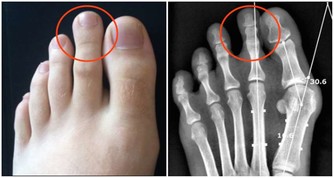

目前中國有1億人左右患有靜脈曲張,靜脈曲張的問題不僅僅是看上去不雅觀,更重要的是,當靜脈曲張累積到深靜脈時,或引起肺栓塞,導致猝死。

讓我們先來回想一下,靜脈曲張的形成原因主要有哪兩個?一是先天性的血管壁薄弱,這一點我們沒法干預;另外一個原因是久坐久站,姿勢不正確。這個是完全可以改正的。因此,避免靜脈曲張的關鍵就是避免久站久坐。